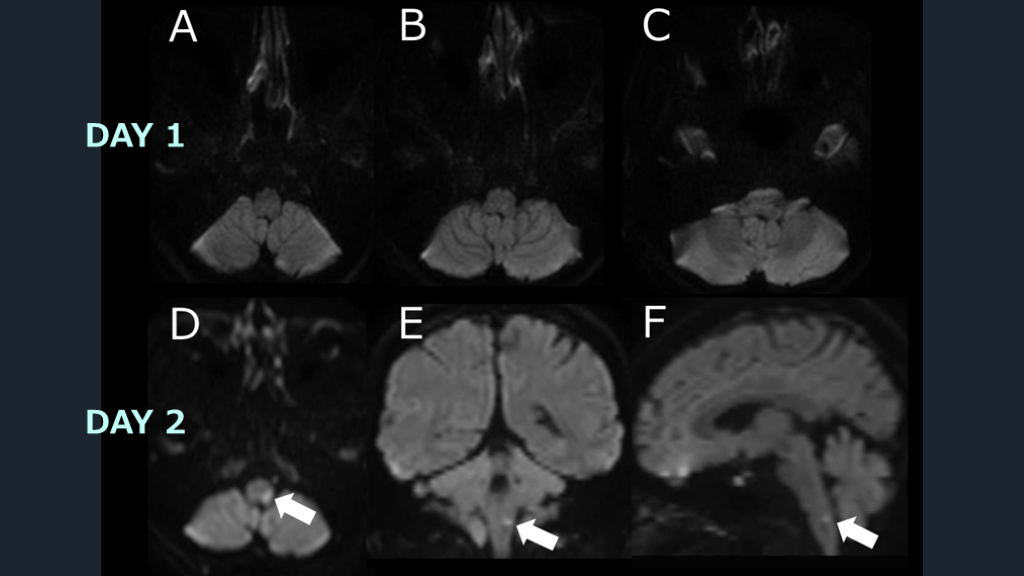

MRIの偽陰性を 克服するために① 後者に関しては、MRI検査は結果が偽陰性の可能性がありうる、という前提で診療を進めていく必要がある。そして、DWI偽陰性は2つの要因で起こりうることを押さえておく。1つは、MRI施行が発症早期の場合に起こりうる「時間的偽陰性」の要因である。もう1つは後方循環系脳梗塞で起こりうる「部位的偽陰性」の要因である。そして脳幹部梗塞ではこの部位的偽陰性が多いことが知られている。時間的偽陰性を克服するためには、「入院後に時間を空けて2回目のMRIを再検すること」で克服可能である。

MRIの偽陰性を 克服するために② 部位的偽陰性を克服するためには、「DWIの2方向(水平断に加えて冠状断を追加)の撮像」で克服可能である。撮像方向を加えることで見落としを減らすことが出来る。以上より、現実的な対応は次の如くとなる。通常のプロトコールの撮像で初回MRI検査におけるDWIが陰性だったとする。その場合、「入院翌日に、DWIを2方向で再度撮像する」ことで、時間的・空間的偽陰性を排除することが可能になる。MRIを診断の切り札として行う脳梗塞診療の偽陰性によるピットフォールも慎重に意識することで、脳梗塞診断は不安を減らすことが出来る。

脳梗塞を診断するためのDWIの感度は92%、特異度は75%とされる10)。DWIは発症後1時間以内の脳梗塞を特定できる。ただし、脳梗塞の約7%は DWIで陰性になりうる11)。DWI陰性の脳梗塞患者は先述のごとく、脳幹部梗塞で多く報告される。例えばMLF症候群や片麻痺症状を呈するラクナ梗塞の場合によく経験される。後方循環障害による脳梗塞患者は、前方循環障害の脳梗塞患者よりも DWIが陰性となる可能性が5倍高くなる。最初のDWIが陰性だった脳梗塞疑いの患者の約3分の1が、2回目のスキャンで高信号に変化した、という報告もある10)。 DWIは信じられない? Eur J Radiol Open. 2023 Nov 4:11:100533.

先述の如く、脳幹部梗塞疑いの場合には1度のMRI検査でも脳梗塞は否定しきれない、という意識は重要である。症候的に脳幹部梗塞の可能性が示唆されるにも関わらずDWI陰性だった場合には、2度目のMRI撮影を行うというアクションが重要である。 この場合には脳梗塞に準じて入院対応とし、2回目のMRI検査を行う。時間的・部位的偽陰性を克服するための「2回目のDWIによる2方向撮像」を活用し、診断を明らかにしていく。 DWIの偽陰性を克服する。

DAY 1 DAY 2